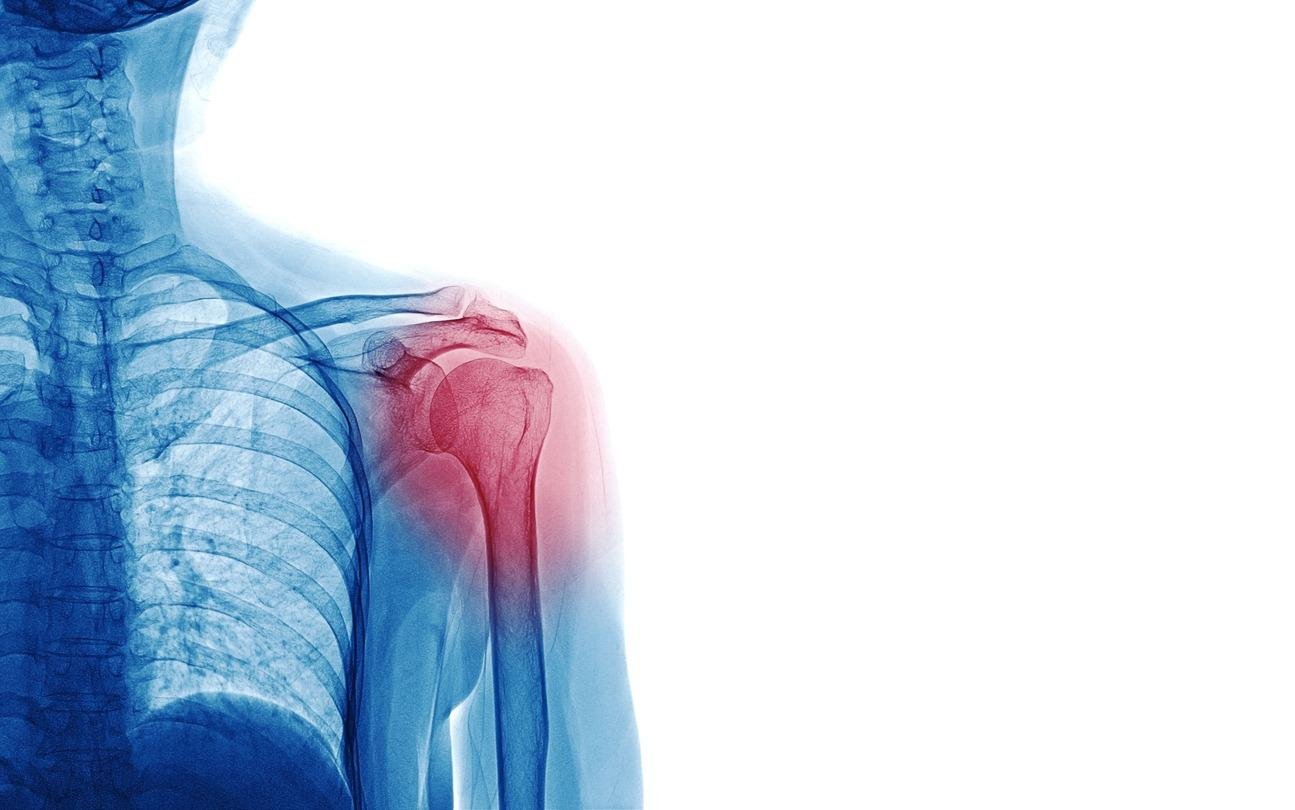

What Is a Shoulder Dislocation?

The shoulder is a ball-and-socket joint where the upper arm bone fits into the shoulder socket. The labrum is a ring of cartilage that deepens the socket and helps keep the ball in place. When the shoulder dislocates, the upper arm bone slips out of the socket, often tearing the labrum in the process.

Shoulder dislocations typically occur due to sports injuries, falls, or direct trauma to the shoulder. They frequently happen with a sudden popping sensation, severe pain, visible deformity of the shoulder, and immediate inability to move the arm. Most dislocations are anterior, meaning the ball moves forward out of the socket.